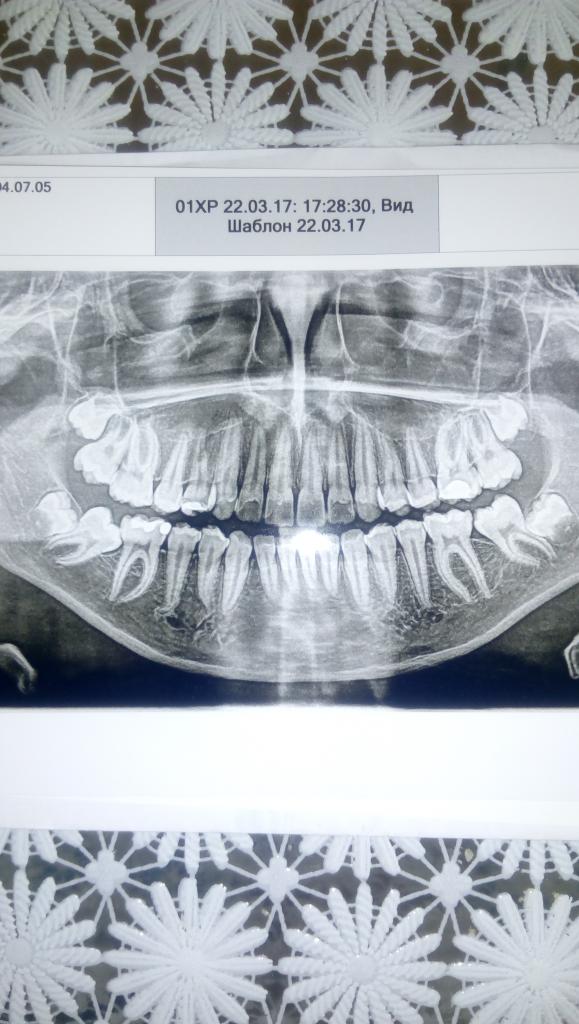

Добрый день. Ситуация следующая. Ребенку 12 лет. В 10 поставили брекеты, т.к. была большая скученнось, зубы на другие зубы заходили, некоторые были повернуты на 90' и тд. Были все, кроме 8. Сняли брекеты, все отлично было, носили и носим капы. Сейчас ребенок начал жаловаться на нижнюю челюсть. Заметили, что один зуб обратно поворачивается. Сделали панорамный снимок. Идут все 8. Нижняя 8 давит на 7, а он на все остальные. 8 в десне. Рекомендуют удалять 8.

Нажмите на изображение для увеличения

Название: IMG_20170327_105445.jpg

Просмотров: 39

Размер:	82.6 Кб

ID:	11954144

Вложение 11954144

Для восьмерок рановатое воздействие на зубной ряд...больше похоже на нижнюю правую семерку с ее косым расположением...почему ее не выставили более вертикально? Хотя, может и все в комплексе... Как правило, ортодонты, чтобы исключить после снятия брекетов подобные последствия, назначают на удаление восьмерок еще до лечения...

Есть снимок 2015 года, там семерка ровно стоит, это она сейчас так легла...Ждать с брекетами уже нельзя было. Ребенок рот стеснялся открыть. Зубы все были перекручены. В 10 лет все уже были постоянные. Несколько зубов на другие заходили сверху. А 8 тогда совсем далеко в десне были. Ортодонтом мы довольны, Крылов, один из лучших в городе.

Хирург сказал после предварительного осмотра, интересный случай...